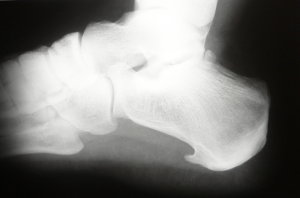

- Fersensporn und Fasciitis plantaris - meist chronische und sehr schmerzhafte Entzündung an Fersenbein und Fußsohle